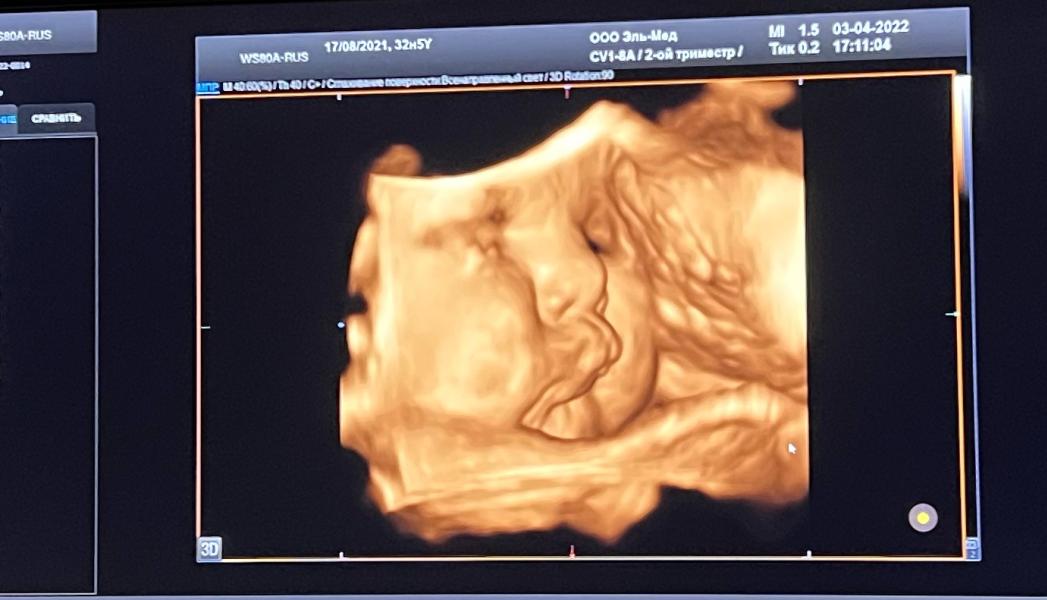

3-е УЗИ на 33 неделе беременности: вес малыша 2454 грамма – какие прогнозы?

Сегодня мы были на 3-м УЗИ🥰

33 нед - 2454 гр🥰

Вот такие мы уже крупненькие😜